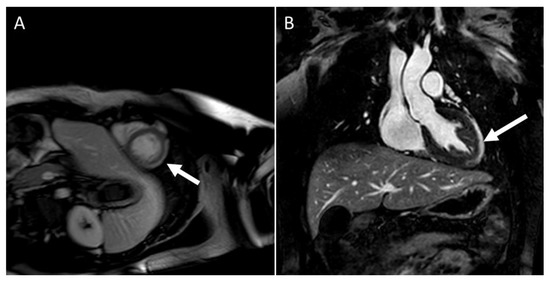

- Theocharis, P.; Wong, J.; Pushparajah, K.; Mathur, S.K.; Simpson, J.M.; Pascall, E.; Cleary, A.; Stewart, K.; Adhvaryu, K.; Savis, A.; et al. Multimodality cardiac evaluation in children and young adults with multisystem inflammation associated with COVID-19. Eur. Heart J. Cardiovasc. Imaging 2021, 22, 896–903. [Google Scholar] [CrossRef]

- Bartoszek, M.; Małek, Ł.; Barczuk-Falęcka, M.; Brzewski, M. Cardiac magnetic resonance follow-up of children after pediatric inflammatory multisystem syndrome temporally associated with SARS-CoV-2 with initial cardiac involvement. J. Magn. Reson. Imaging 2021, 55, 27870. [Google Scholar] [CrossRef]

- Webster, G.; Patel, A.B.; Carr, M.R.; Rigsby, C.K.; Rychlik, K.; Rowley, A.H.; Robinson, J.D. Cardiovascular magnetic resonance imaging in children after recovery from symptomatic COVID-19 or MIS-C: A prospective study. J. Cardiovasc. Magn. Reson. 2021, 23, 86. [Google Scholar] [CrossRef] [PubMed]

- Aeschliman, F.A.; Misra, N.; Hussein, T.; Panaioli, E.; Soslow, J.H.; Crum, K.; Steele, J.M.; Huber, S.; Marcora, S.; Brambilla, P.; et al. Myocardial involvement in children with post-COVID multisystem inflammatory syndrome: A cardiovascular magnetic resonance-based multicenter international study—The CARDOVID registry. J. Cardiovasc. Magn. Reson. 2021, 23, 140. [Google Scholar] [CrossRef] [PubMed]

- Blondiaux, E.; Parisot, P.; Redheuil, A.; Tzaroukian, L.; Levy, Y.; Sileo, C.; Schnuriger, A.; Lorrot, M.; Guedj, R.; le Pointe, H.D. Cardiac MRI in Children with multisystem inflammatory syndrome associated with COVID-19. Radiology 2020, 297, E283–E288. [Google Scholar] [CrossRef] [PubMed]